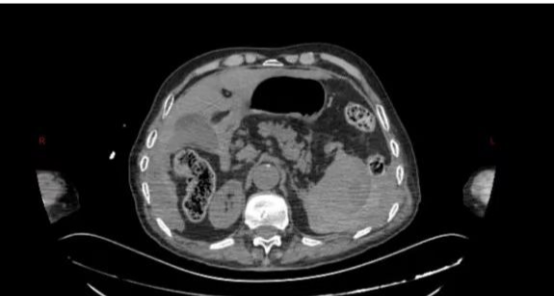

急诊行CT检查提示:脾脏密度不均匀升高,考虑脾破裂。在就诊过程中,患者逐渐出现了心率增快、血压降低,行腹腔穿刺抽出不凝血,结合患者既往病情及辅助检查,考虑脾破裂的可能性极高。

术中,探查可见患者脾脏包膜下巨大血肿并包裹脾脏,包膜表面可见裂口,并伴有活动性出血,考虑迟发性脾破裂。由于患者年龄较大,必须尽量将手术时间缩短,否则随着手术时间的延长,患者术中术后出现麻醉风险及各类并发症的可能将大大增加。然而,脾脏周围密布着脾动脉、胃短动脉等各式各样的血管,如同布满了引线的火药库,想要快速、精准分离脾脏周围组织与血管更是难上加难,即使1毫米的偏差都有可能引发难以控制的大出血。